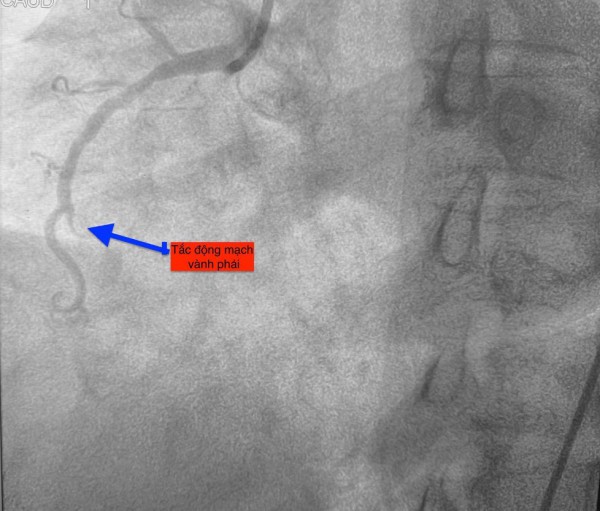

Trường hợp thứ ba, lúc 15 giờ 53 phút, nam bệnh nhân 78 tuổi nhập viện vì đau ngực. Bệnh nhân cho biết đau ngực từng cơn trong 3 ngày, ngày nhập viện thì đau ngực liên tục. Điện tim gợi ý nhồi máu cơ tim cấp; chụp mạch vành cấp cứu phát hiện bệnh nhân cũng tắc động mạch vành phải.

Hình ảnh chụp mạch vành cho thấy các bệnh nhân bị tắc mạch máu tim (do mảng xơ vữa, huyết khối) dẫn đến tình trạng thiếu máu cục bộ và nhồi máu cơ tim cấp

ẢNH: BV